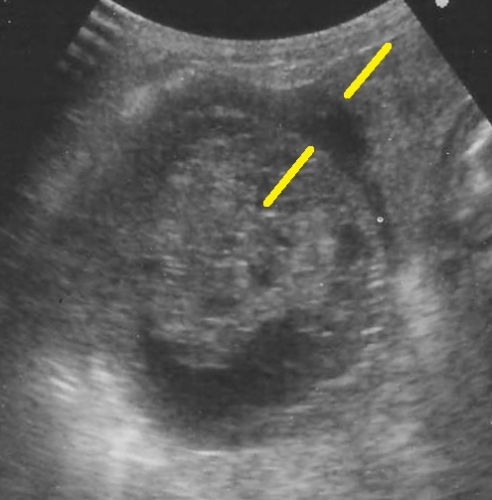

下の超音波像は胆嚢破裂の初期の胆嚢をみたものです。中央部に胆嚢粘液嚢腫がみられますが、黄色腺の間に示されている「三角形の黒いエリア」が胆嚢壁の外側に広がっています。これは胆嚢壁の裂け目から内部の「粘液状物」が腹腔内に出ていたり、周囲の組織との強い癒着や炎症を示す画像です。ご参考までに右が正常の胆嚢です。

上記の患者さんは食欲がなく、頻発する嘔吐と腹部痛を理由に来院いたしました。その後直ちに胆嚢摘出術を実施して事なきを得ています。